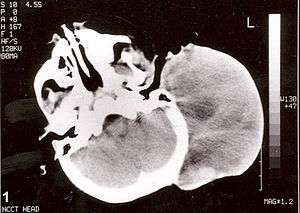

| Non-contrast computed tomography of head showing a large mass without any intracranial extension. The diagnosis was postauricular congenital alveolar rhabdomyosarcoma. | |